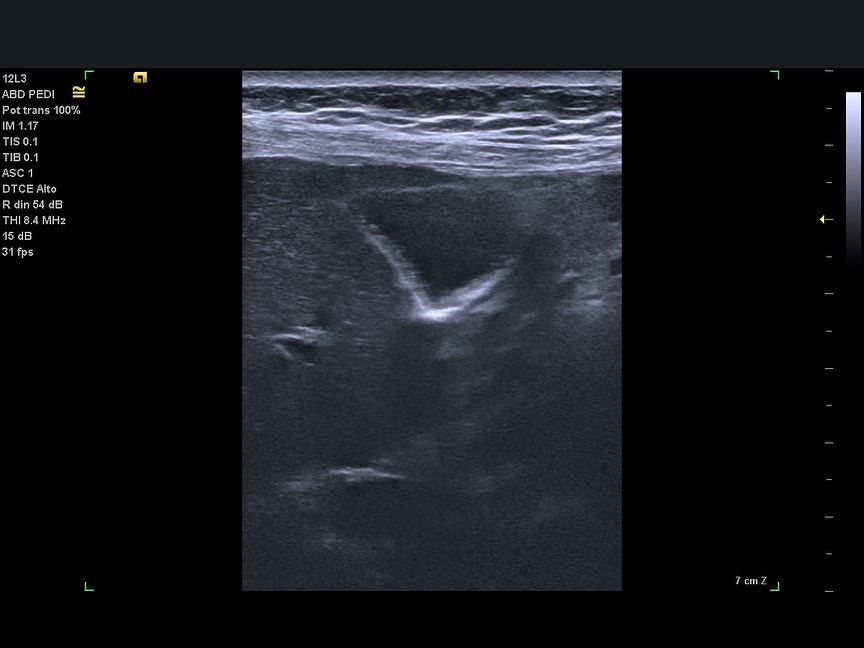

Diferencia sustancial. Es muy aconsejable revisar la vesícula con sonda de baja y de alta frecuencia.

🔴 Procesos inflamatorios de la pared vesicular, Adenomiomatosis,pequeños pólipos,son mucho más visibles con la sonda de alta frecuencia, que es un recurso espectacular que aumenta clarísimamente el diagnóstico de patología en esta localización.

Observa las diferencias entre las imágenes, solo cambia una cosa, el transductor…[Sólo😉]